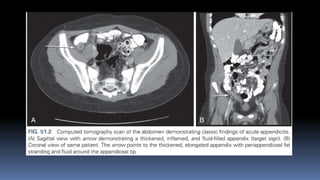

CT-

scan

• Features on a CT scan that suggest appendicitis include

Enlarged lumen and double wall thickness (greater than 6 mm)

Wall thickening (greater than 2 mm)

Periappendiceal fat stranding

Appendiceal wall thickening and/or

An appendicolith

• 10.

CT- scan • Features ona CT scan that suggest appendicitis include Enlarged lumen and double wall thickness (greater than 6 mm) Wall thickening (greater than 2 mm) Periappendiceal fat stranding Appendiceal wall thickening and/or An appendicolith